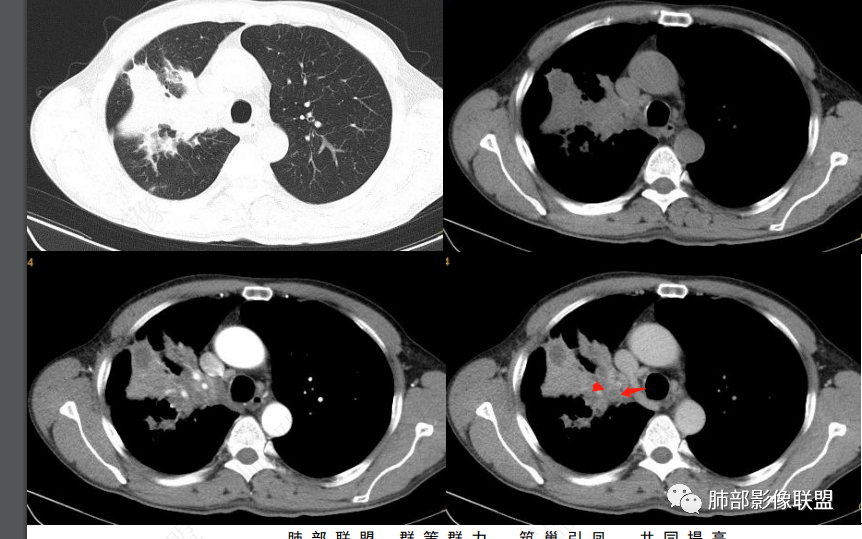

这是炎性的,支气管壁弥漫增厚,近端腔狭窄

这是肺癌的

这是腔内肺癌的